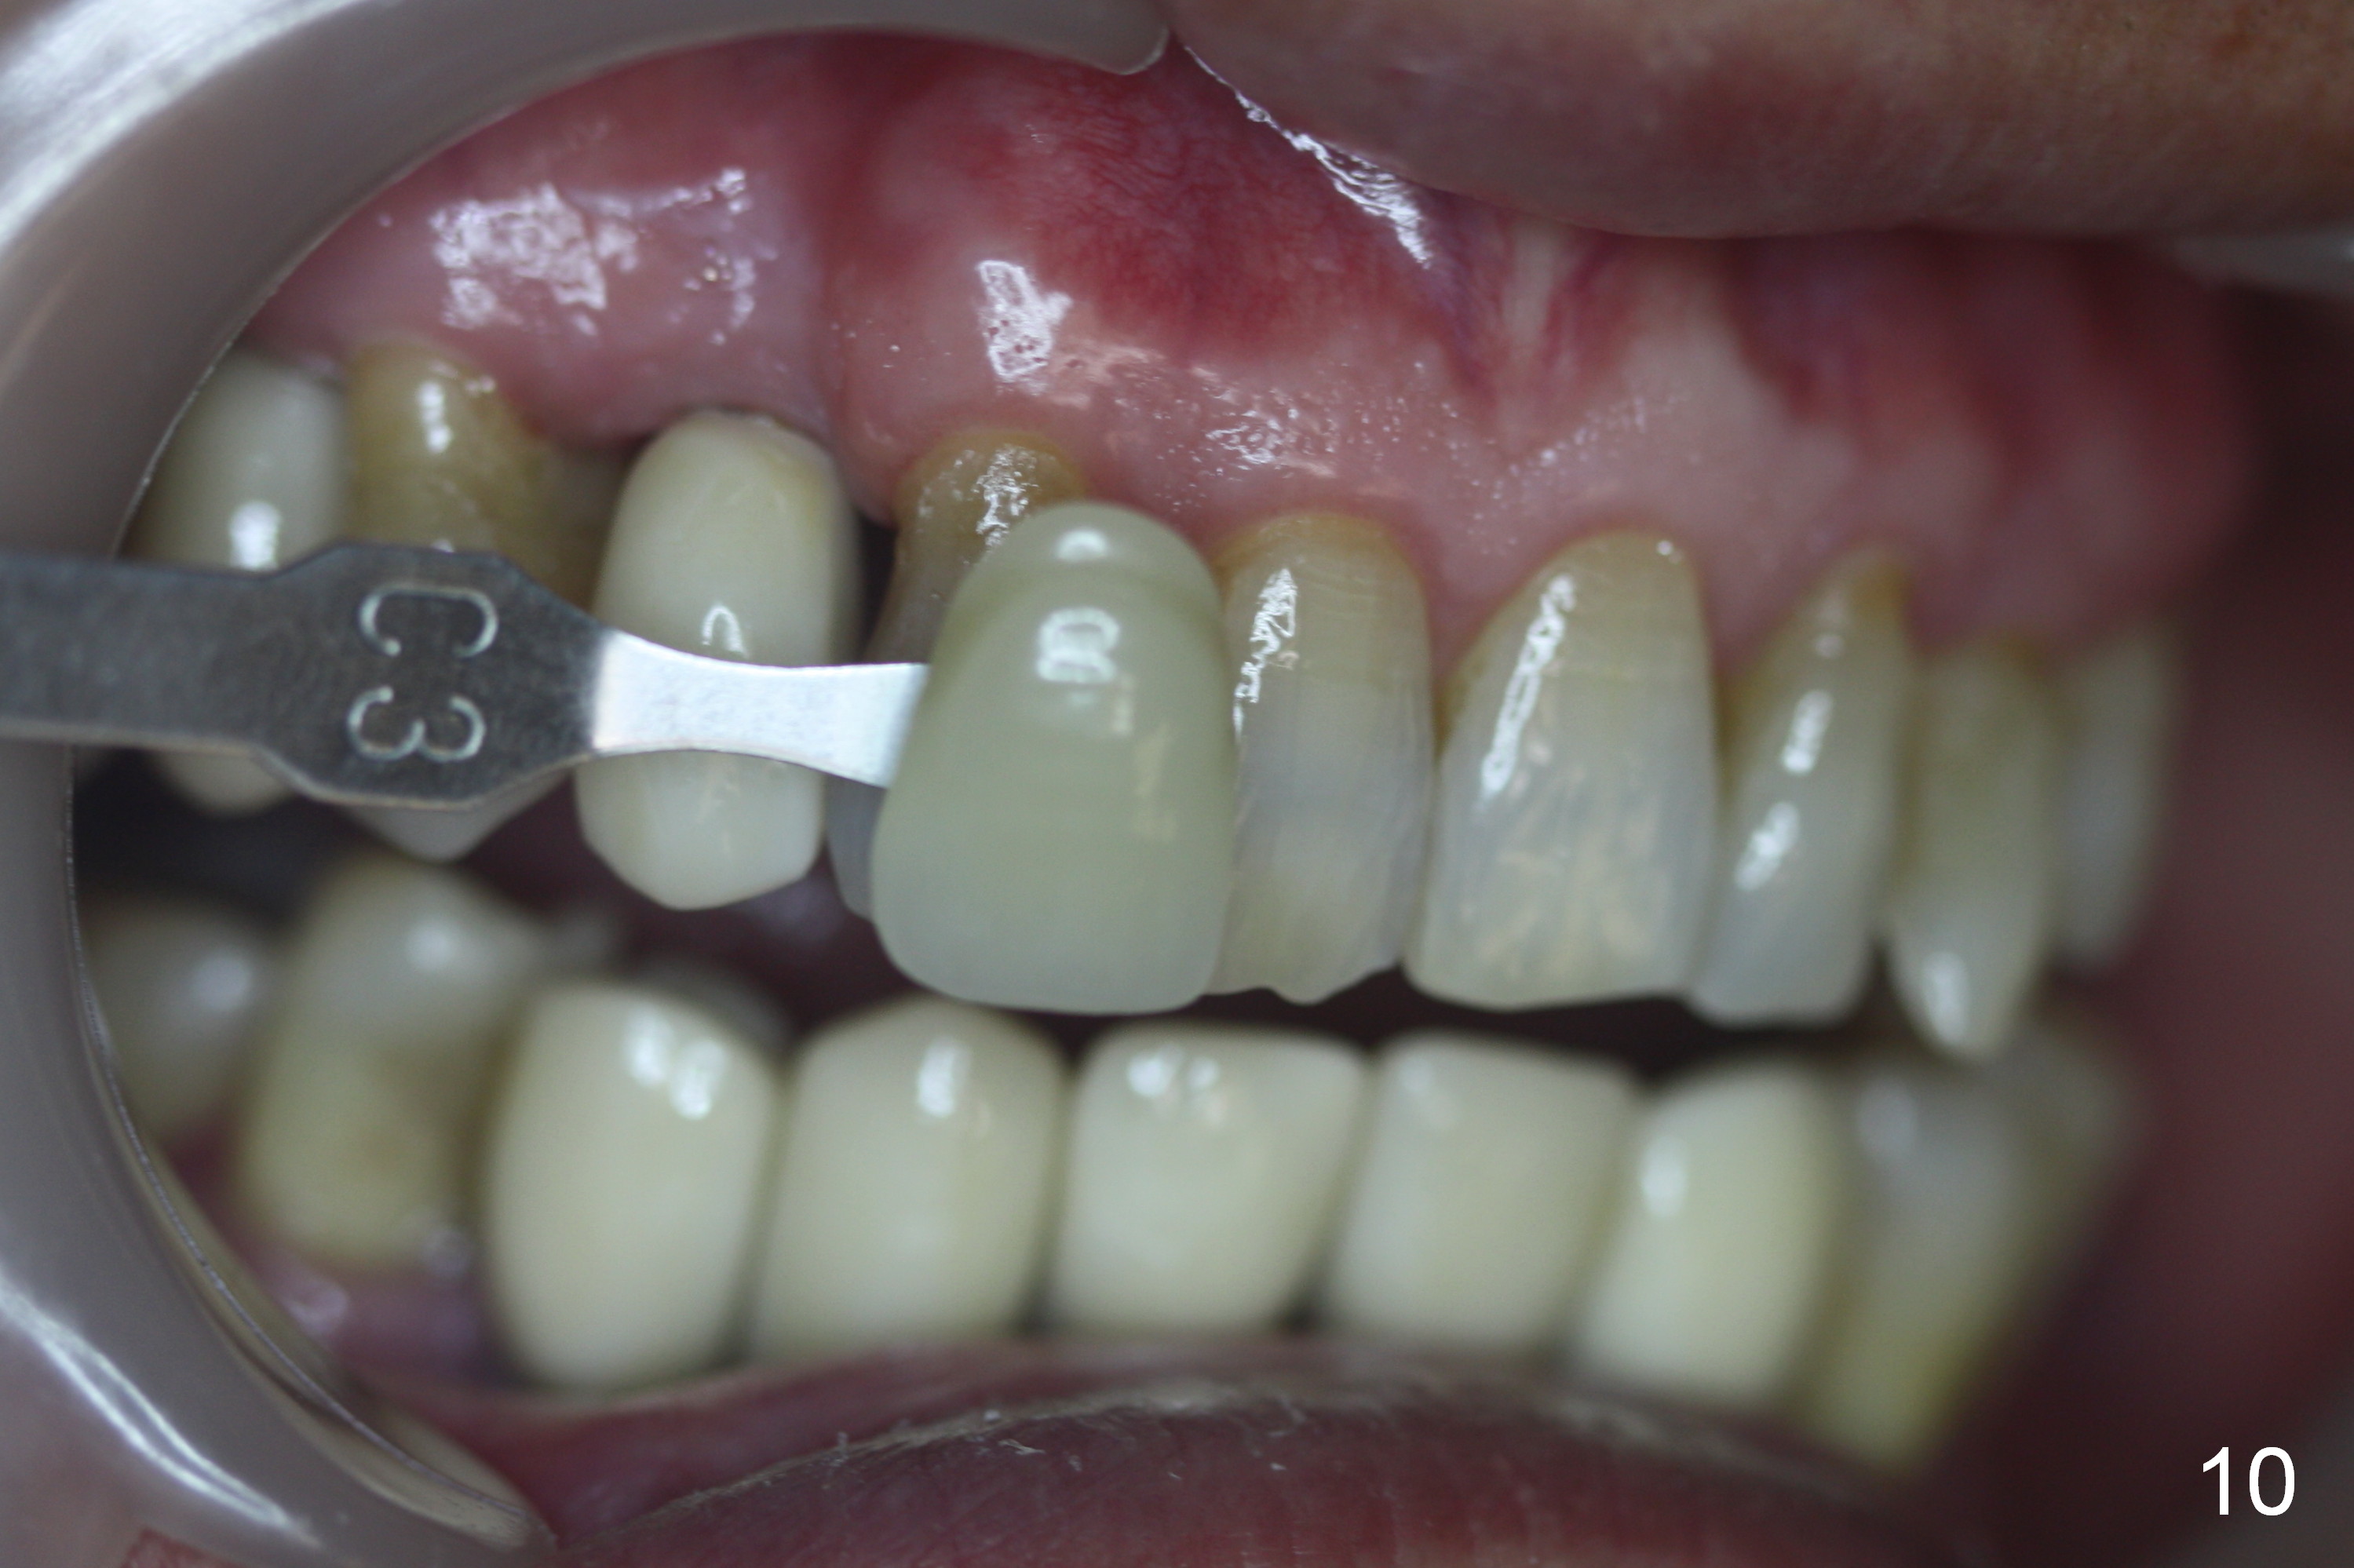

When the final crowns are seated, the shade is off.  It appears that C3 is appropriate (Fig.10,11).  Please make the crowns more transparent.